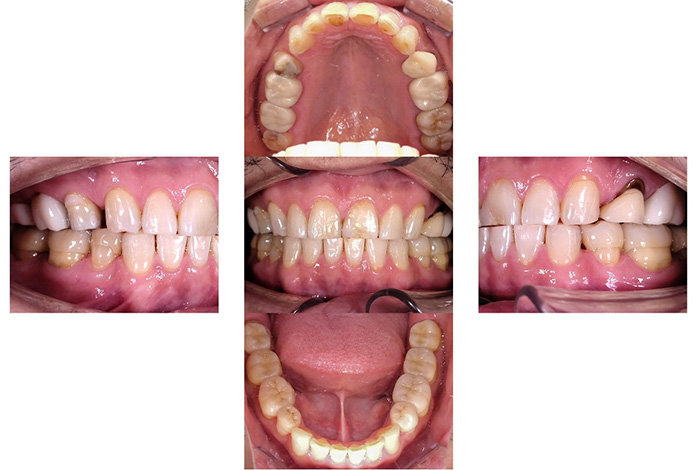

Before

After

【矯正治療】マウスピース型矯正装置(インビザライン)による全顎矯正

【補綴治療】詳細は表内の費用欄に掲載

【矯正治療】10か月

【補綴治療】約5か月

【矯正治療】12回

【補綴治療】14回

【矯正治療】¥957,000(税込)

【補綴治療】